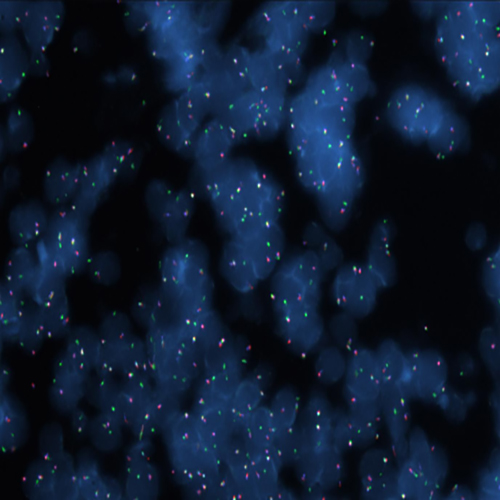

Hybridization of MYC TC break probe to a tissue section showing aberrant pattern (1GBR1G1BR).

RUO - MYC (8q24) Triple-Color, Break (tissue)

Rearrangements of the proto oncogene MYC c-myc) have been consistently found in Burkitt's lymphoma tumor cells. In cases with the common t(8;14) chromosomal translocation, the MYC gene is translocated to chromosome 14 and rearranged with the immunoglobulin heavy chain genes; the breakpoint occurs 5' to the MYC gene and may disrupt the gene itself. In Burkitt's lymphoma showing the variant t(2;8) or t(8;22) translocations, the genes coding for the k and l immunoglobulin light chain are translocated to v-myc avian myelocytomatosis viral oncogene homolog (MYC or c-myc) chromosome 8. The MYC (8q24) Break probe is optimized to detect rearrangements involving the 8q24 locus in a triple-color, split assay on formalin fixed paraffin embedded tissue.